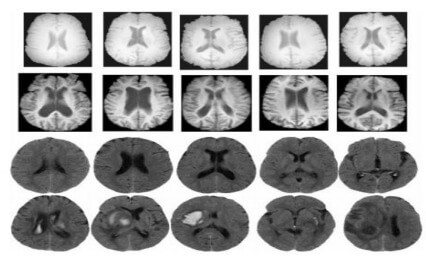

Figure 1

Figure 1: MRI images of healthy and unhealthy brains

Furthermore, the brain is the main organ of personality, character, judgment, and innovation. So, when your brain works right, your work is excellent; and when your brain has trouble, you are much more likely to have trouble in your life. With a healthier brain, it is fairly clear that you are happier, healthier, wealthier, wiser, and more creative. The health of the brain either accelerates innovation or decelerates it, and the thing that affects your brain health is your behavior. Your behaviors and what you learn every day affect the brain directly in the way of neuroplasticity. By using MRI technology, we can get images of the brain as shown in figure 1 where the first and third rows belong to the "Normal" category whereas the second and fourth rows belong to the "Abnormal" category [3] .